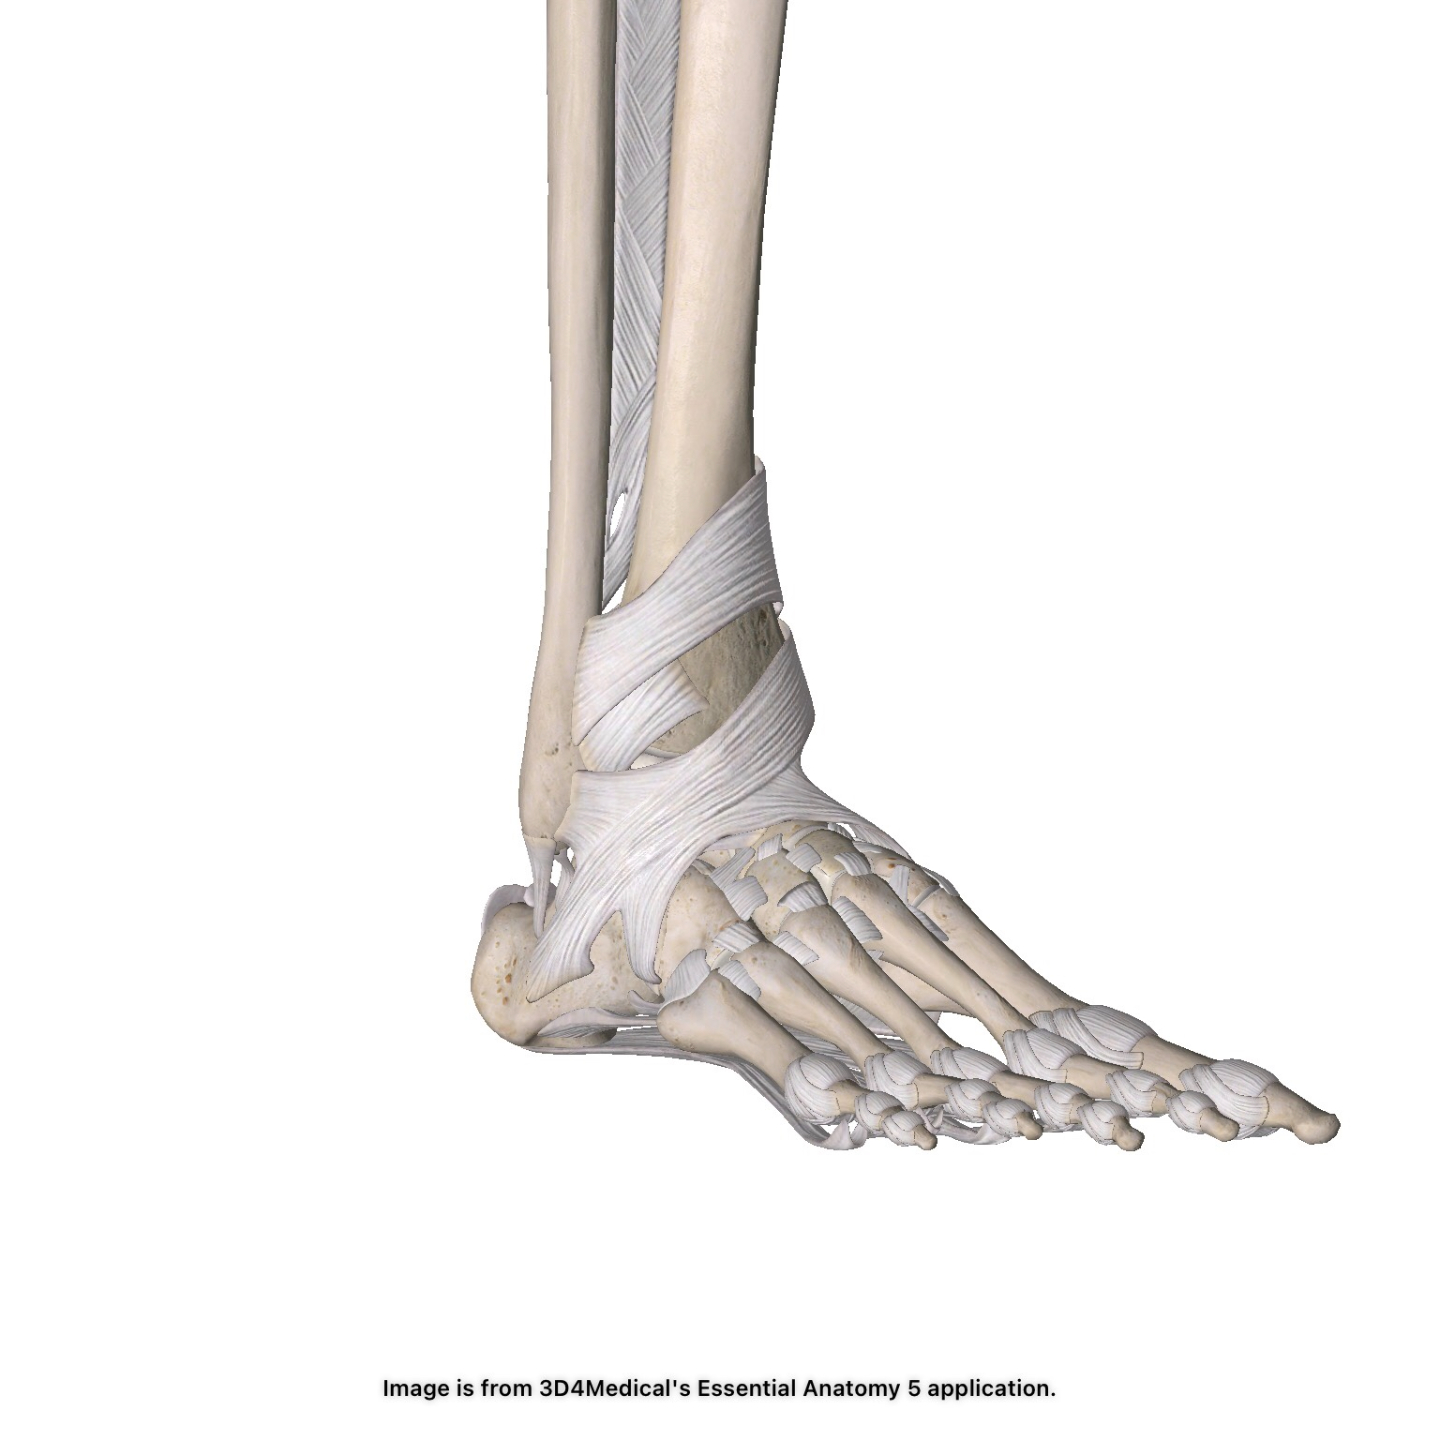

Ankle Sprains: 3 Steps Physicians Should Follow

Ankle sprains are one of the most common orthopedic injuries. When working with patients, physicians should follow these three steps in order to get the patient back into action quickly and safely.